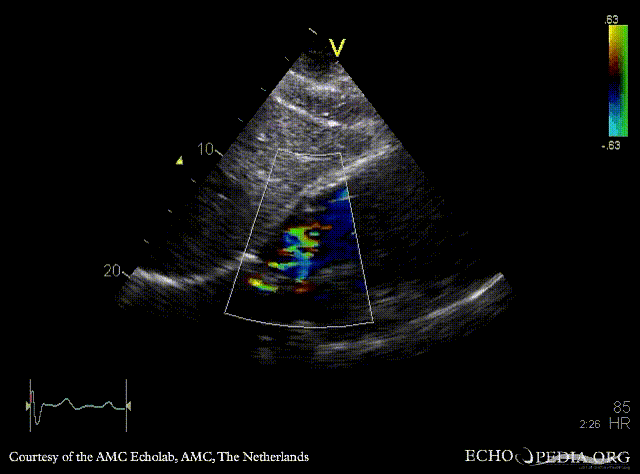

E00308.gif E00309.gif

PLAX: right ventricle enlargement in patient with ASD type II PSAX: right ventricle enlargement and diastolic flattening of the IVS